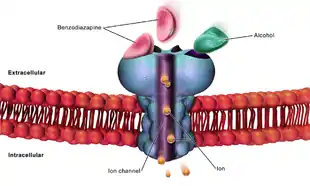

Higher order functioning of the cerebral cortex is organized by the cerebellum. In those with cerebral atrophy, Purkinje cells, or the cerebellar output neurons, in the vermis are reduced in number by 43%.[7] This large reduction in Purkinje cells causes a decrease in high order cerebral cortex organization. The cerebellum is also responsible for refining crude motor output from the primary motor cortex. When this refinement is missing, symptoms such as unsteadiness and ataxia[7] will present. A potential cause of chronic alcoholic cerebellar dysfunction is an alteration of GABA-A receptor. This dysfunction causes an increase in the neurotransmitter GABA in cerebellar Purkinje cells, granule cells, and interneurons leading to a disruption in normal cell signaling.[7]

Binge drinkers and alcoholics who go through multiple detoxifications show prefrontal cortex dysfunction, as it is known that alcohol has long-term effects on prefrontal cortex function, leading to impairments in executive control tasks. Animal studies show that repeated alcohol withdrawals are associated with a significantly impaired ability to learn new information.[11] Alcohol's acute effects on GABAergic enhancement and NMDA suppression cause alcohol induced neurotoxicity and kindling, or worsening of alcohol withdrawal symptoms with each subsequent withdrawal period. This may cause CNS depression leading to acute tolerance to these withdrawal effects. This tolerance is followed by a damaging rebound effect during withdrawal. This rebound causes hyperexcitability of neurotransmission systems. If this hyperexcitability state occurs multiple times, kindling and neurotoxicity can occur leading to increased alcohol-related brain damage. Damaging excitotoxicity may also occur as a result of repeated withdrawals. Similar to people who have gone through multiple detoxifications, binge drinkers show a higher rate of emotional disturbance due to these damaging effects.[11]